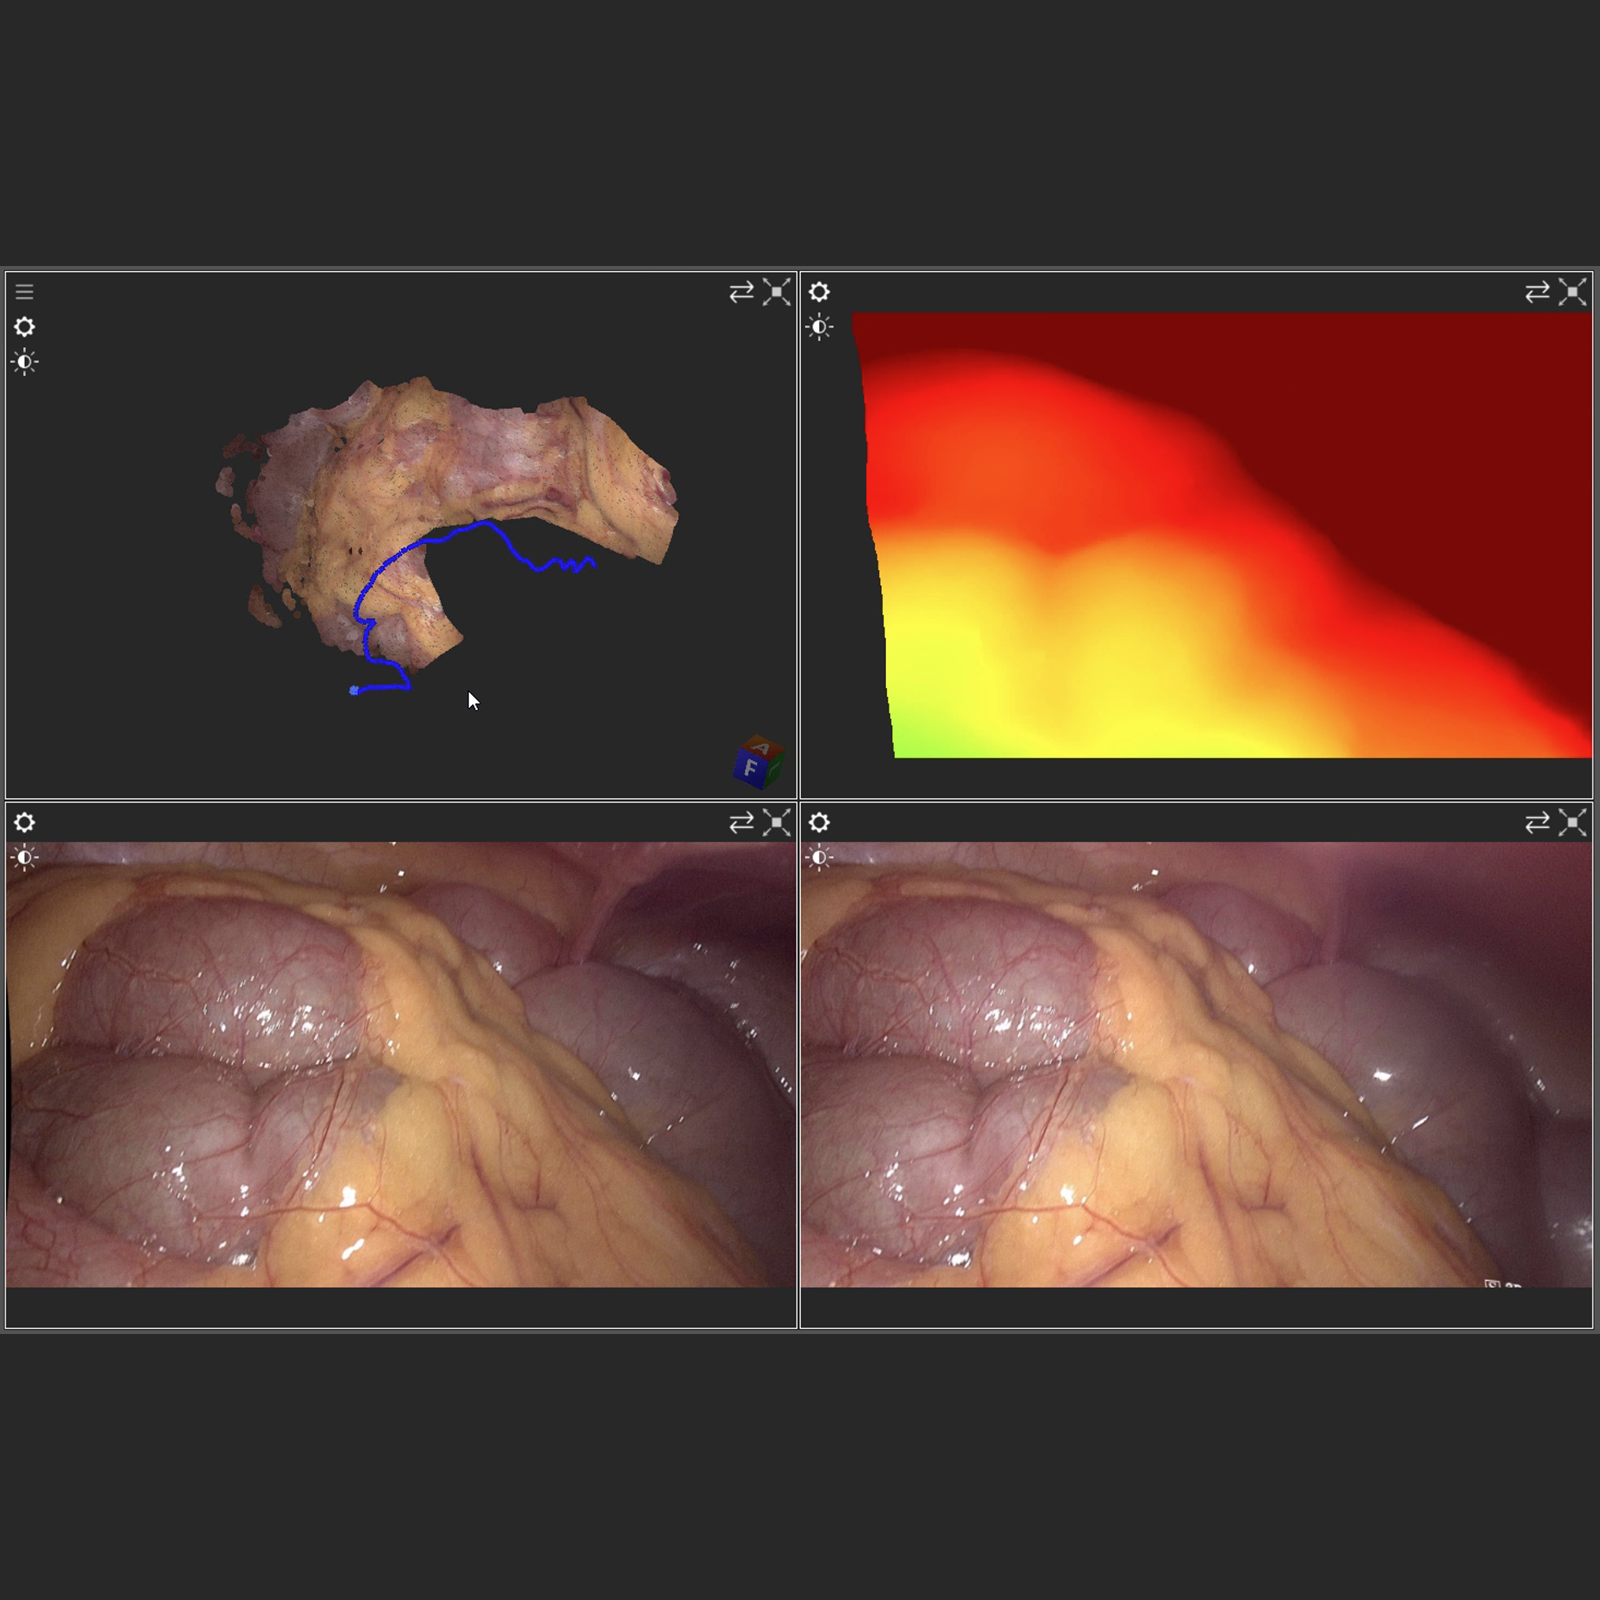

Endoscopic Stereo SLAM

This video shows our endoscopic SLAM pipeline on stereoscopic video of a laparoscopic screening procedure.

The stereo input is converted to a depth map using a state-of-the art learning based stereo depth estimation network. The resulting color + depth stream is then fed into our surfel-based SLAM pipeline.